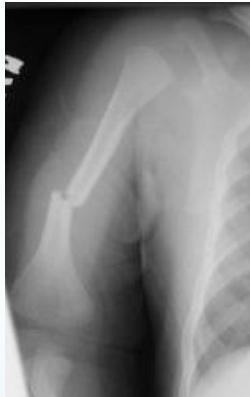

- Humeral shaft fracture

- <3 years of age

Case Example:

- 12-year-old girl

- History of trauma

- Mild tenderness

- Periosteal reaction

- Initially diagnosed as injury

- 2 months later, still tender

- Final diagnosis: Ewing’s sarcoma